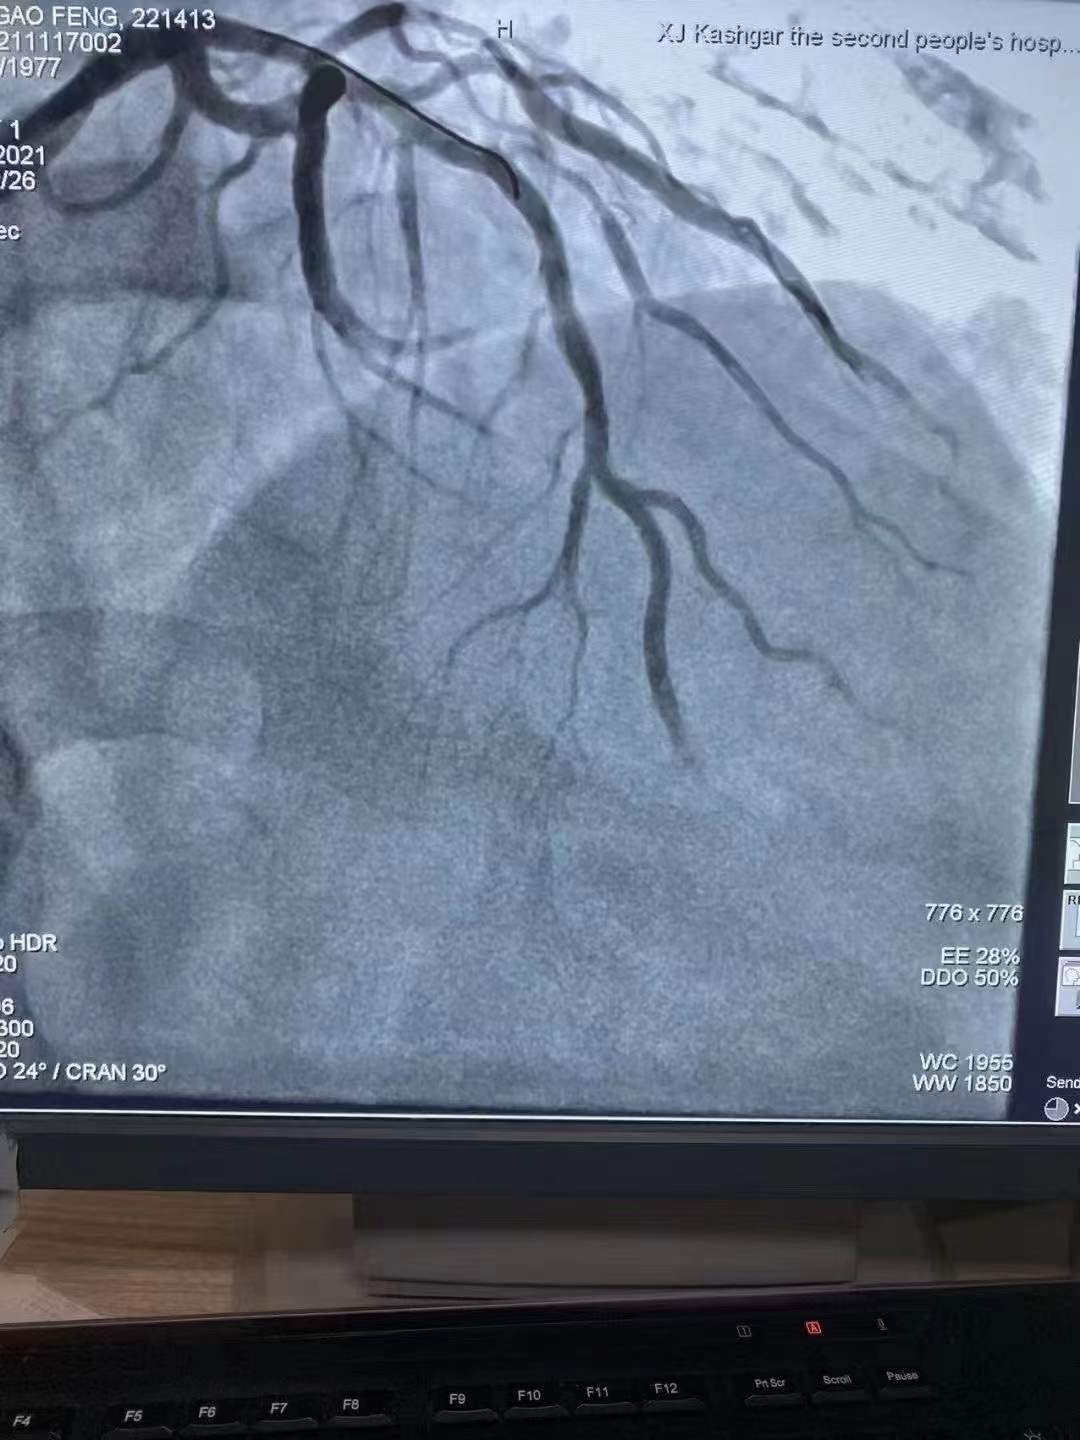

完美修復(fù)心歸自然情系邊疆

祝賀 新疆喀什地區(qū)第二人民醫(yī)院心內(nèi)科在復(fù)旦大學(xué)中山醫(yī)院援疆專家姚志峰主任帶領(lǐng)下成功為患者植入新疆首例Xinsorb生物可吸收支架,感謝援疆項(xiàng)目的扎實(shí)落地,溫暖了新疆各族百姓Xinsorb與白衣天使共同守護(hù)每一個心臟!